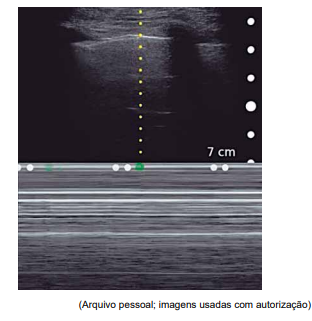

Realizou-se a ultrassonografia “point-of-care” conforme imagem a seguir, no modo M, vista em todo hemitórax direito (aspecto de “código de barras”).

Considerando esses achados, qual é a conduta adequada para a condição apresentada pelo paciente?

Realizou-se a ultrassonografia “point-of-care” conforme imagem a seguir, no modo M, vista em todo hemitórax direito (aspecto de “código de barras”).

Considerando esses achados, qual é a conduta adequada para a condição apresentada pelo paciente?